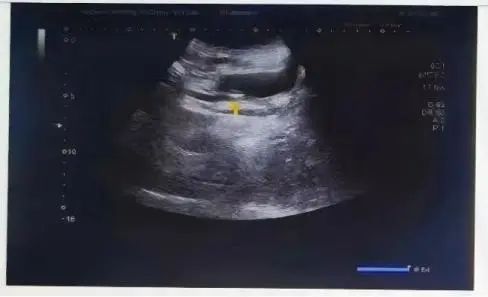

贾女士的输尿管结石位于输尿管膀胱开口处,大小约14mm*7mm,未与输尿管黏膜粘连,为快速碎石创造了有利条件。

贾女士结石影像